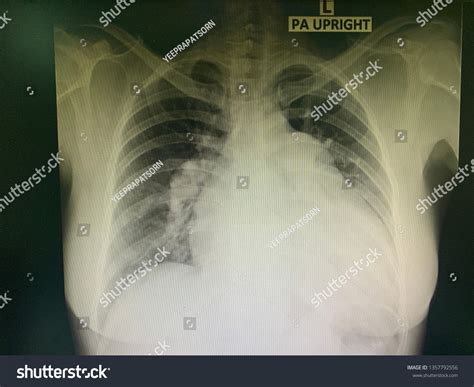

Pleural Effusion

Pleural effusion is the accumulation of fluid in the pleural space. It appears as a layer of fluid along the chest wall or as a meniscus sign on the lateral view. Common causes include heart failure, pneumonia, and malignancy.